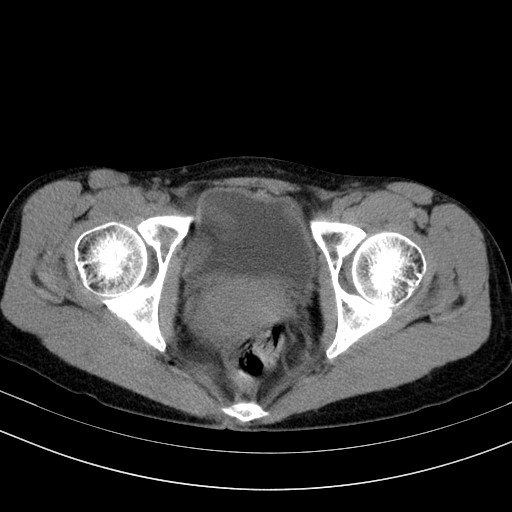

以下是引用卜一在2009-4-7 5:08:00的发言:[br]宫颈癌可能。支持!

以下是引用随光逐影在2009-4-7 8:17:00的发言:[br]考虑宫颈占位性病变(宫颈癌?);建议行进一步检查。

以下是引用jiangjing在2009-4-7 16:46:00的发言:[br]宫颈增大,结构不清,右侧附件区可疑囊样占位,建议增强及mri 检查